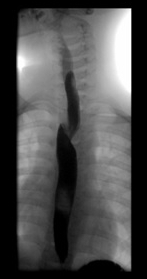

En primer lugar realizamos un tránsito esofagogastroduodenal con contraste de bario porque es una prueba fácil, barata, rápida y que aporta mucha información en la patología del tracto gastrointestinal. Elegimos esta prueba fundamentalmente para valorar posibles compresiones extrínsecas o estenosis esofágicas.